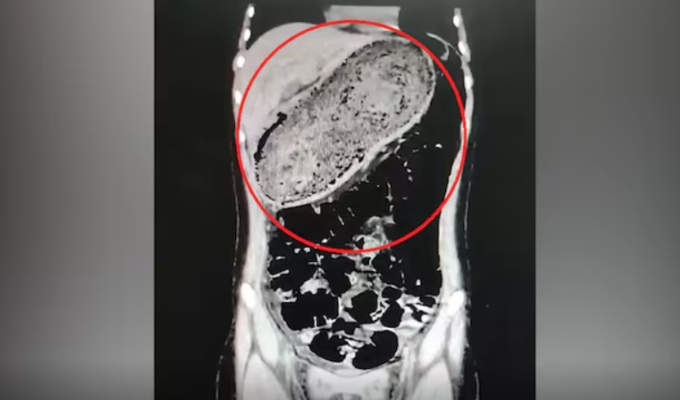

Los galenos le realizaron diversos exámenes para detectar la razón del dolor, pues los calmantes no le hacían efecto. Luego de algunas horas, se confirmó que la paciente tenía un tricobezoar de 3.5 kilos, se trata de una rara tumoración por acumulación de cabellos y restos de comida.

Con este hallazgo, se decidió programar una operación, la cual duró un aproximado de 4 horas. El equipo logró la extracción de la malformación sin causar daños en el área abdominal.